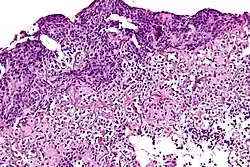

Biopsja i badanie histopatologiczne

.jpg)

Biopsja umożliwia pobranie materiału do badania histopatologicznego i ustalenie ostatecznego rozpoznania kostniakomięsaka[30]. Jest wykonywana po wykonaniu badań obrazowych i postawieniu radiologicznego (klinicznego) podejrzenia kostniakomięsaka[7]. Powinna być wykonana w ośrodku doświadczonym w leczeniu mięsaków kości[126]. Miejsce wykonania biopsji jest wybierane na podstawie badań obrazowych i scyntygrafii kości oraz zasadą najkrótszego odcinka pomiędzy guzem a skórą[126]. Miejsce pobrania materiału powinno znajdować się daleko od pęczków naczyniowo-nerwowych, a następnie miejsce biopsji powinno zostać wycięte w ramach ostatecznego leczenia[10]. Konieczne jest uzyskanie żywego utkania tkanki nowotworowej oraz zrębu nowotworu[126].

Biopsja może być wykonana metodą otwartą lub gruboigłowo[30]. Biopsja otwarta jest podstawową metodą biopsji w przypadku mięsaków kości, jest przeprowadzana w znieczuleniu ogólnym i polega na wycięciu całego guza lub reprezentatywnego fragmentu guza[131]. Jednak otwarta biopsja wiąże się z większym ryzykiem rozsiania komórek nowotworowych w prawidłowych tkankach[30].

Część ośrodków ma odpowiednie doświadczenie do oparcia diagnostyki i leczenia o biopsję gruboigłową lub trepanobiopsję[126]. Biopsja gruboigłowa pobrana z kilku miejsc guza może być wystarczającą metodą do uzyskania reprezentatywnych bioptatów[30]. Metoda pozwala ustalić rozpoznanie u 88–96% chorych[126] i w doświadczonych ośrodkach stanowi alternatywę dla biopsji metodą otwartą[9]. Biopsja gruboigłowa wiąże się z mniejszym ryzykiem rozsiewu komórek nowotworowych w zdrowych tkankach niż metoda otwarta. W celu zwiększenia skuteczności diagnostycznej biopsja może być wykonywana pod kontrolą USG lub TK[30]. Miejsce wykonania biopsji powinno być oznaczone nacięciem lub tatuażem[132]. Biopsja cienkoigłowa pozwala jedynie na wykonanie badania cytologicznego i nie ma większej roli w diagnostyce mięsaków kości[30]. Ostateczne rozpoznanie jest stawiane na podstawie badania histopatologicznego materiału pobranego na drodze biopsji operacyjnej lub oligobiopsji[10].